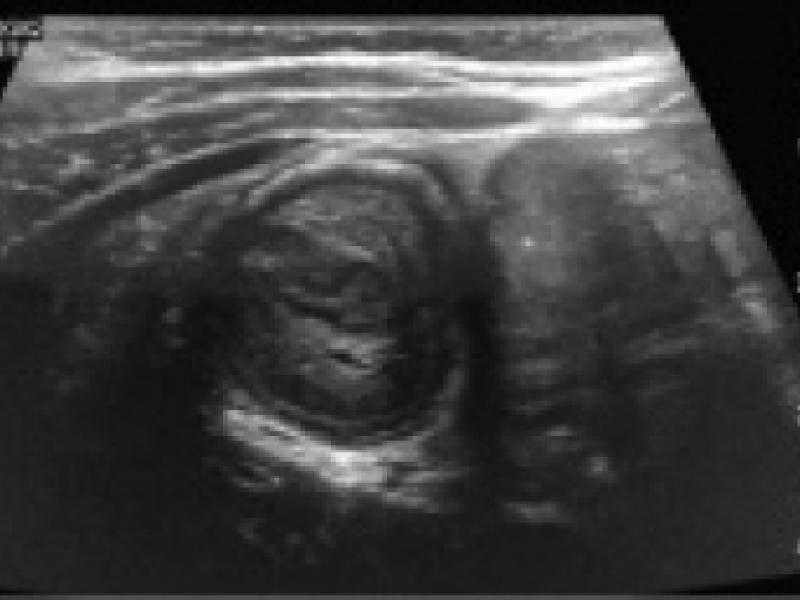

2 year-old male with no PMHx is brought to the ED for